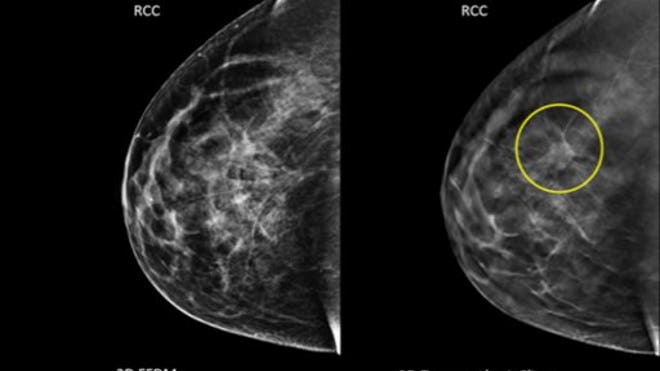

Standard mammograms typically take one image of each breast from two positions, while 3-D scans take several images of different layers of each breast. That allows for the detection of tumors that might be hidden under breast tissue and not noticeable on regular images, said Jim Culley, a spokesman for Hologic, which makes mammogram machines, including the combo ones used in the study that take both kinds.

The detection rates were about four cancers per 1,000 conventional scans versus about five cancers per 1,000 combined 3-D scans.